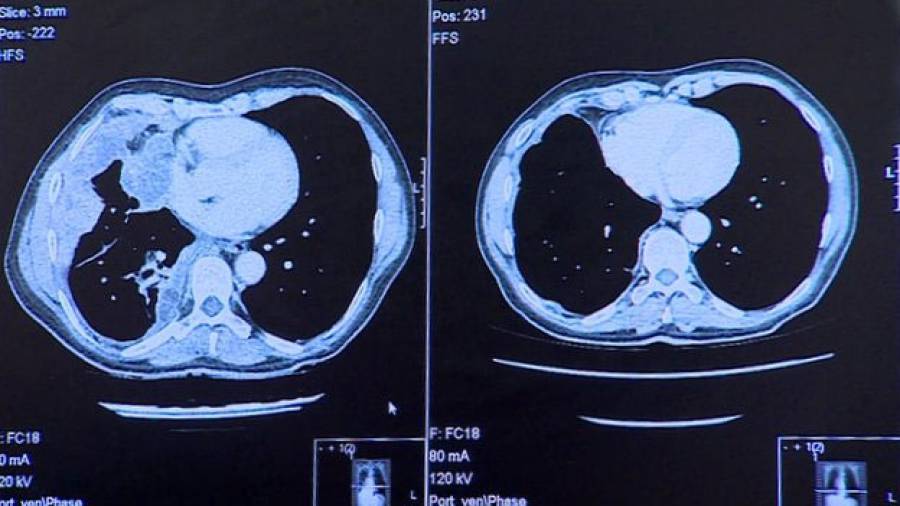

Cientistas desenvolvem medicamentos que alimentam as esperanças para a cura do câncer de pele. A descoberta foi anunciada durante a conferência anual da Sociedade Americana de Oncologia Clínica (Asco), realizada no início deste mês, em Chicago (EUA). O pembrolizumab e o nivolumab foram desenvolvidos para estimular o sistema imunológico a combater os tumores. Os medicamentos atuam bloqueando os caminhos biológicos utilizados pelas células cancerígenas na tentativa de evitar que sejam detectadas pelo sistema imunológico humano.

As duas substâncias foram testadas em portadores de câncer de pele em estágio avançado em diversas partes do mundo. Os resultados foram considerados "animadores e impressionantes" por cientistas.